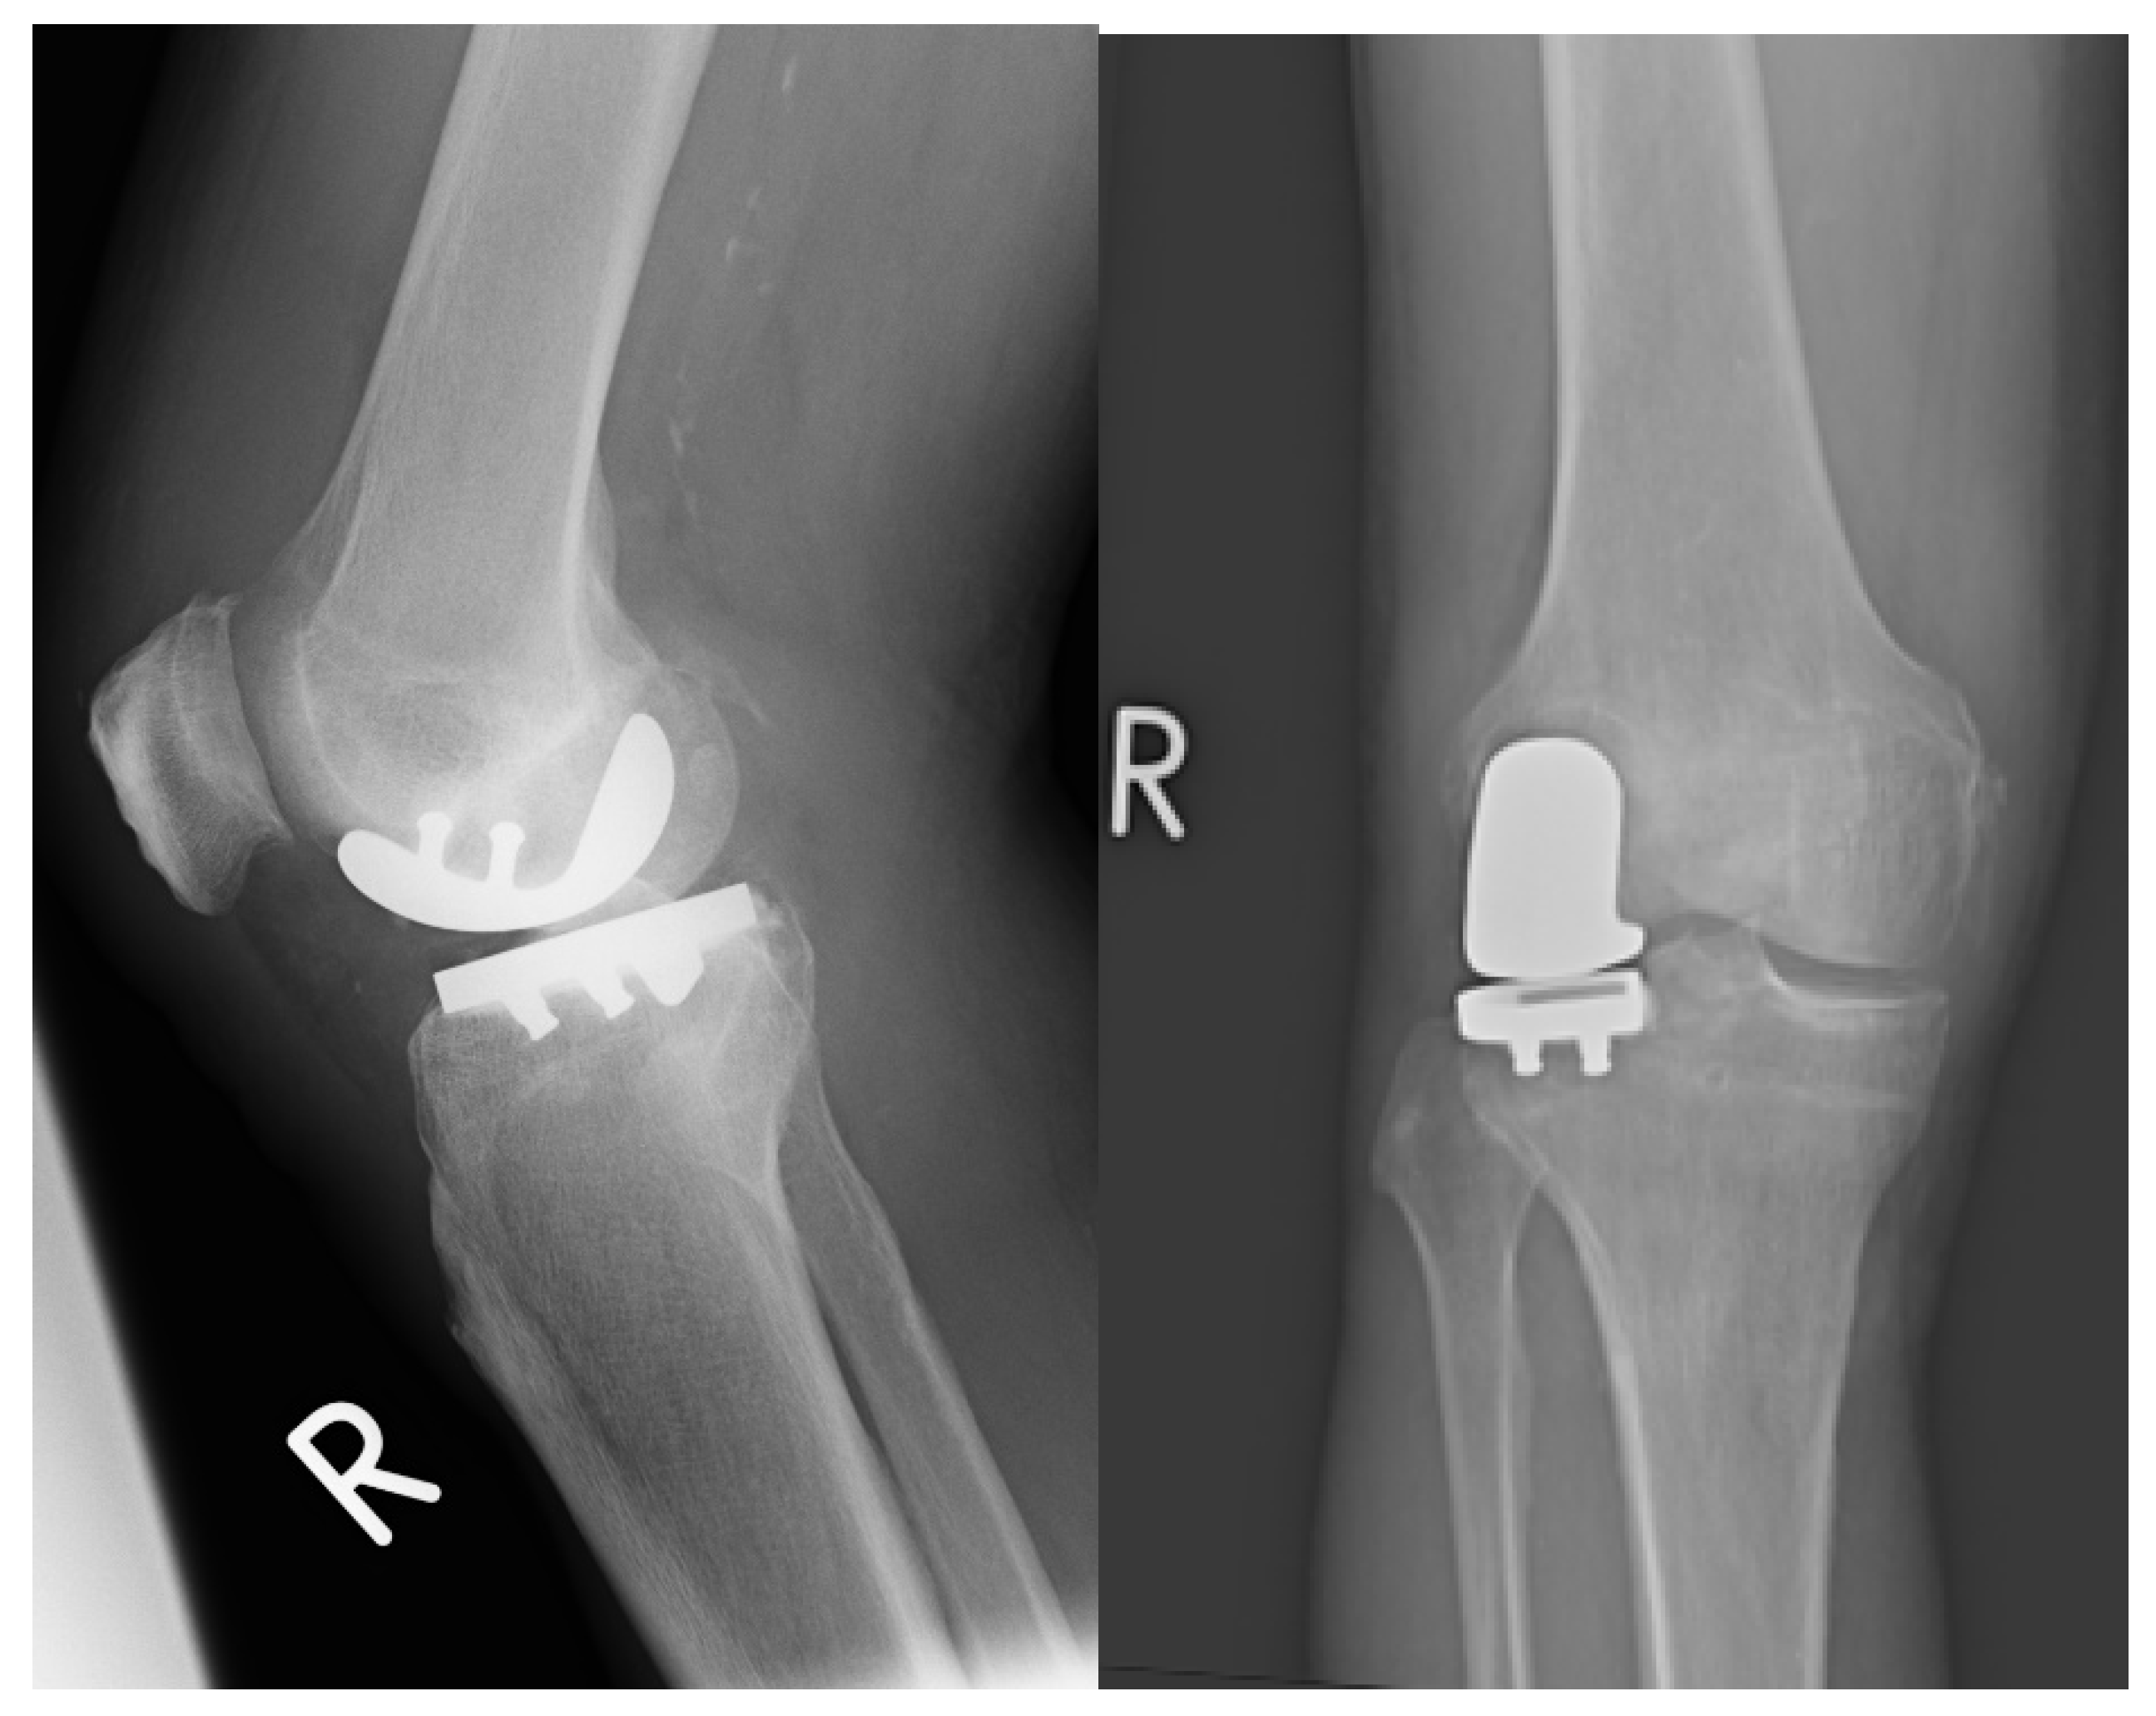

2.1. Prosthesis and Surgical Technique